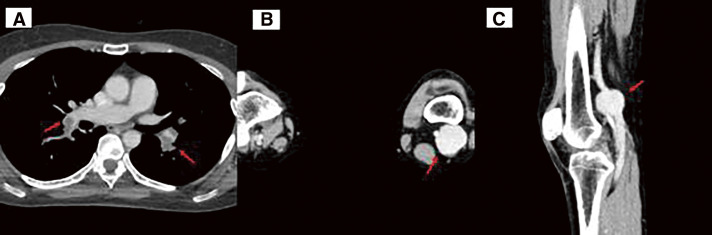

腘静脉动脉瘤(PVA)是一种罕见的血管疾病。我们报告了一例通过进一步评估肺栓塞(PE)导致的心脏骤停(CA)而发现的 PVA 病例。众所周知,PVA 会导致 PE,但很少有 PVA 导致 CA 的报道。医生为患者实施了切向动脉瘤切除术和侧支静脉切开术。患者术后恢复顺利。在进行造影剂增强计算机断层扫描以寻找 CA 的病因时,应考虑到 PVA,因此建议对膝关节以下部位进行筛查。随访1年,未发现并发症。

A popliteal venous aneurysm (PVA) is a rare vascular disorder. We report a case of PVA discovered through further evaluation of sudden cardiac arrest (CA) caused by a pulmonary embolism (PE). It is well-known that PVA causes PE; however, there are few reports of PVA causing CA. A tangential aneurysmectomy and lateral venorrhaphy were performed. The patient's postoperative course was uneventful. When contrast-enhanced computed tomography is performed to search for the cause of CA, PVA should be considered and thus, screening below the knee is recommended. At 1-year follow-up, there were no complications.